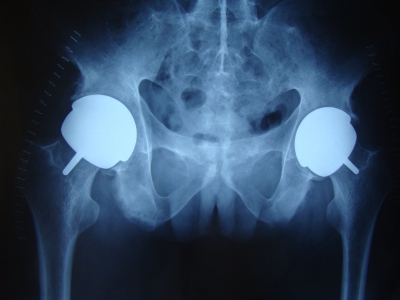

1. 主要体征X 线表现股骨头塌陷,股骨头内有硬化带(分界线),软骨下有新月征,无关节间隙狭窄,髋臼无异常见(图1)。

图1 X 线表现股骨头内有硬化带,软骨下有新月征